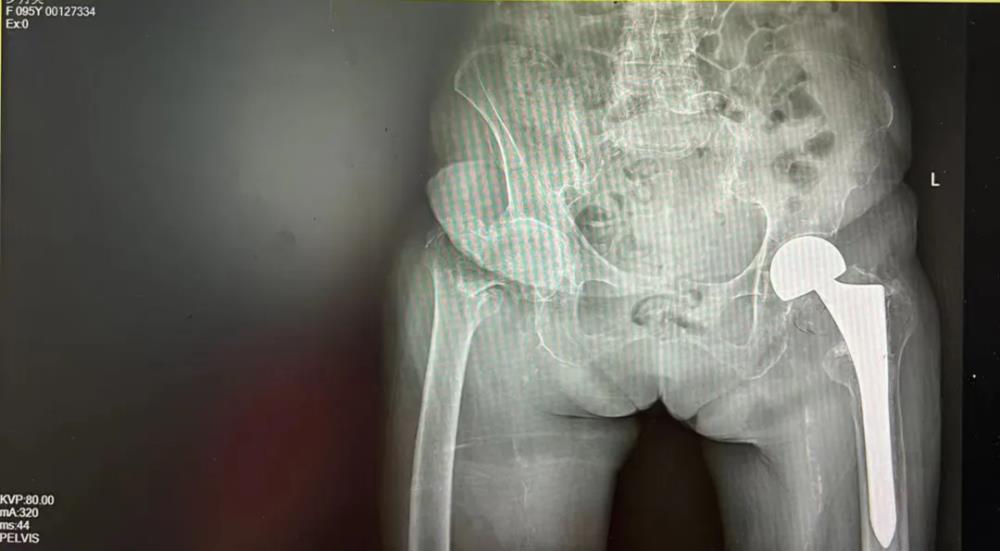

百岁人生,再启新程:近百岁老人成功完成第二次髋关节置换术

钦州市浦北县有这样一位老人,岁月在她的脸上刻下了深深的痕迹,却未能磨灭她眼中的光芒。罗奶奶,今年97岁高龄,是邻里间公认的“不老松”。然而,岁月不饶人,4年前的一次意外导致罗奶奶左股骨粗隆间骨折,在当地医院经过一次成功的髋关节置换手术后,重新站了起来。但是在今年8月初她不慎跌倒致右股骨粗隆间骨折,家属再次送到当地医院欲行手术治疗,当地医院行冠脉造影提示冠心病(三支病变,部分节段严重狭窄),认为其体质较虚弱合并严重的内科疾病,手术风险较高,不敢为其手术。随后家属带着罗奶奶住院资料到我院门诊咨询,外科与内科医生了解病情后告知家属有信心调理稳定罗奶奶的内科疾病,创造手术机会。听到医生的建议,家属急忙把罗奶奶转到我院,等待下一步的检查和治疗。

手术室内,我院髋关节二科团队凭借精湛的技术和丰富的经验,小心翼翼地进行着每一步操作。经过1小时的努力,手术终于圆满成功。当罗奶奶被推出手术室,那一刻,亲人攥紧的心都松了下来,掌声与泪水交织在一起,为罗奶奶的勇气和医生的精湛技术喝彩。